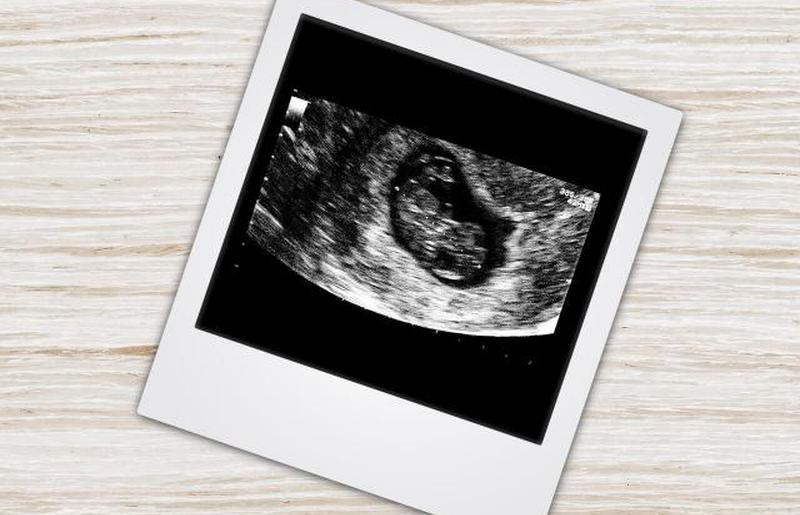

Во время Почему УЗИ для беременных так важно вы сможете увидеть своего ребенка, который будет выглядеть как маленький шарик арахиса, желточный мешок и пуповину. Ваш врач, вероятно, не сможет проверить наличие двойни, но к концу первого триместра у вас будет лучшее представление об этом. Потеря нескольких детей довольно распространена, поскольку они часто могут прятаться друг за другом или настолько малы, что их трудно найти в растущей матке. Ваш врач распечатает снимок УЗИ, который вы сможете забрать домой на память. Вы можете добавить это в рамку или Бесплатные страницы детских книг для печати если хотите.

Ребенок все еще выглядит довольно странно в этот момент. Руки-ножки начинают развиваться, но пока больше похожи на почки. Ультразвуковое изображение будет больше похоже на каплю, чем на ребенка, но все это очень быстро изменится. Большая часть веса ребенка приходится на голову, а тело все еще изогнуто с намеком на хвост. Ребенок составляет около 1/4 до дюйма в длину .

УЗИ — отличный способ начать общение с малышом. Через Удивительные события на 7 неделе беременности вы сможете из первых рук увидеть сердце вашего ребенка, его общий размер и общий рост во время беременности.